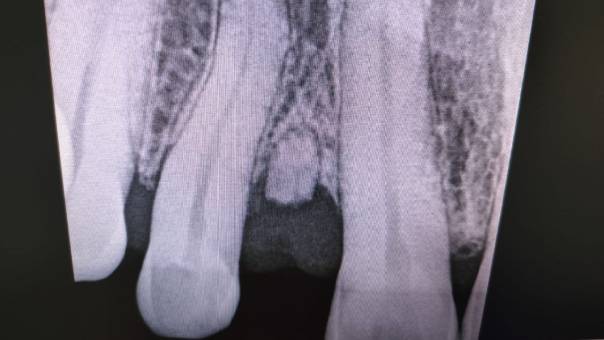

Radiograph after extraction of the mesioden

Radiographs after Rootcanal treatment